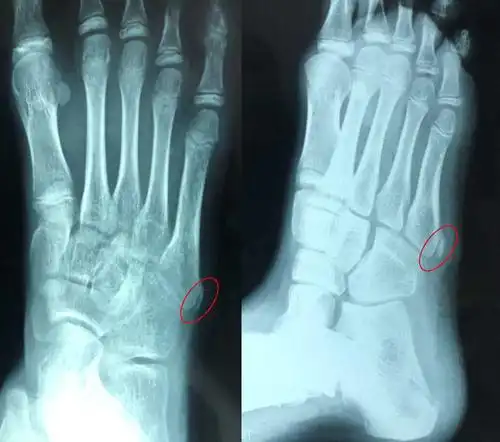

儿童踝关节外翻 [病例帖]

1岁6个月宝宝脚裸下有骨头突出左右脚对称求问各宝妈有这样的情况吗

小朋友活动后足外侧疼痛明显,到底是怎么回事?_疼痛 - 好大夫在线